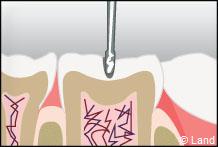

Les traitements possibles pour les stades de la carie où seuls l’émail et la dentine sont touchés, peuvent se faire au composite.

Si la cavité de carie est trop importante, il peut poser des problèmes d’étanchéité avec le temps.